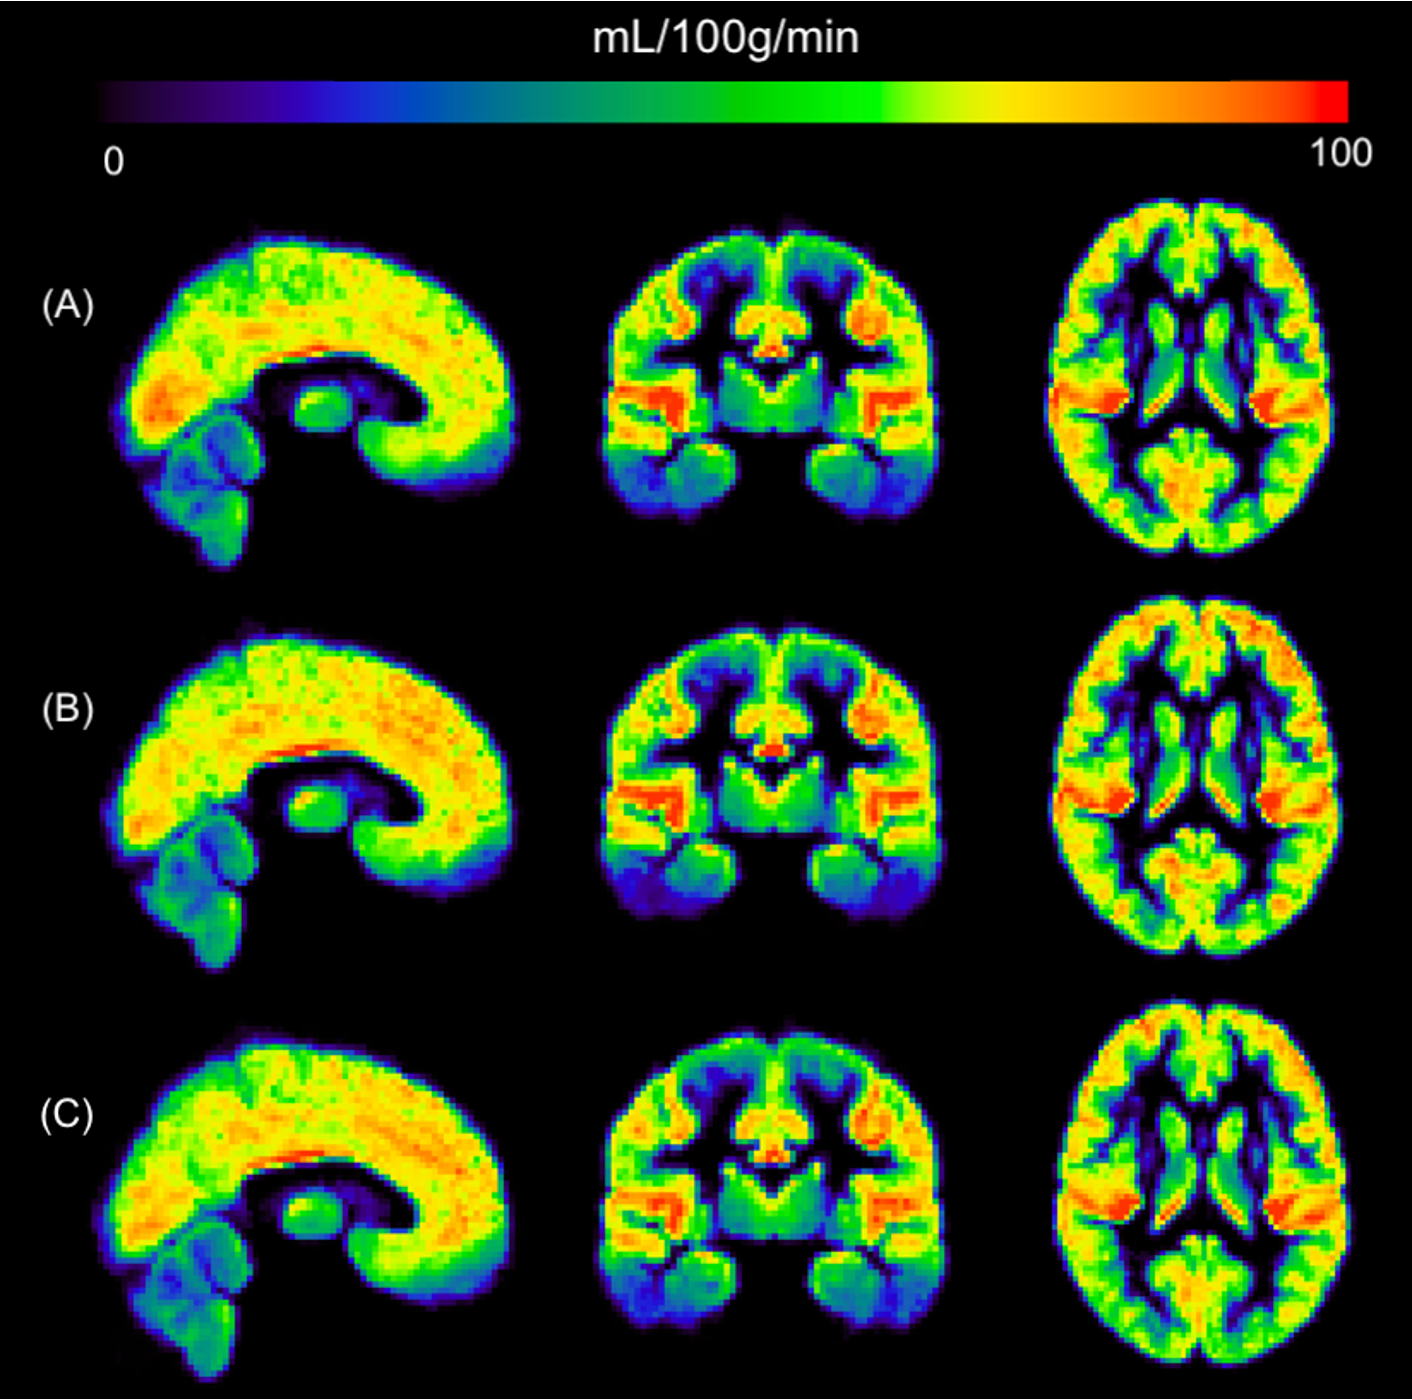

Picture1

Figure 1. PRE > MID. Paired grey matter (GM) CVR difference map expressed in t-values (paired t-test; n=16; p<0.05). Significant decreases in CVR are shown in the left putamen and bilaterally in the cingulate and paracingulate gyrus. Images are in MNI space.

• Our results demonstrate that nonconcussive head impacts may lead to decreased CVR and possibly increased CBF, suggesting vascular dysfunction2 and compensatory hyperemia7